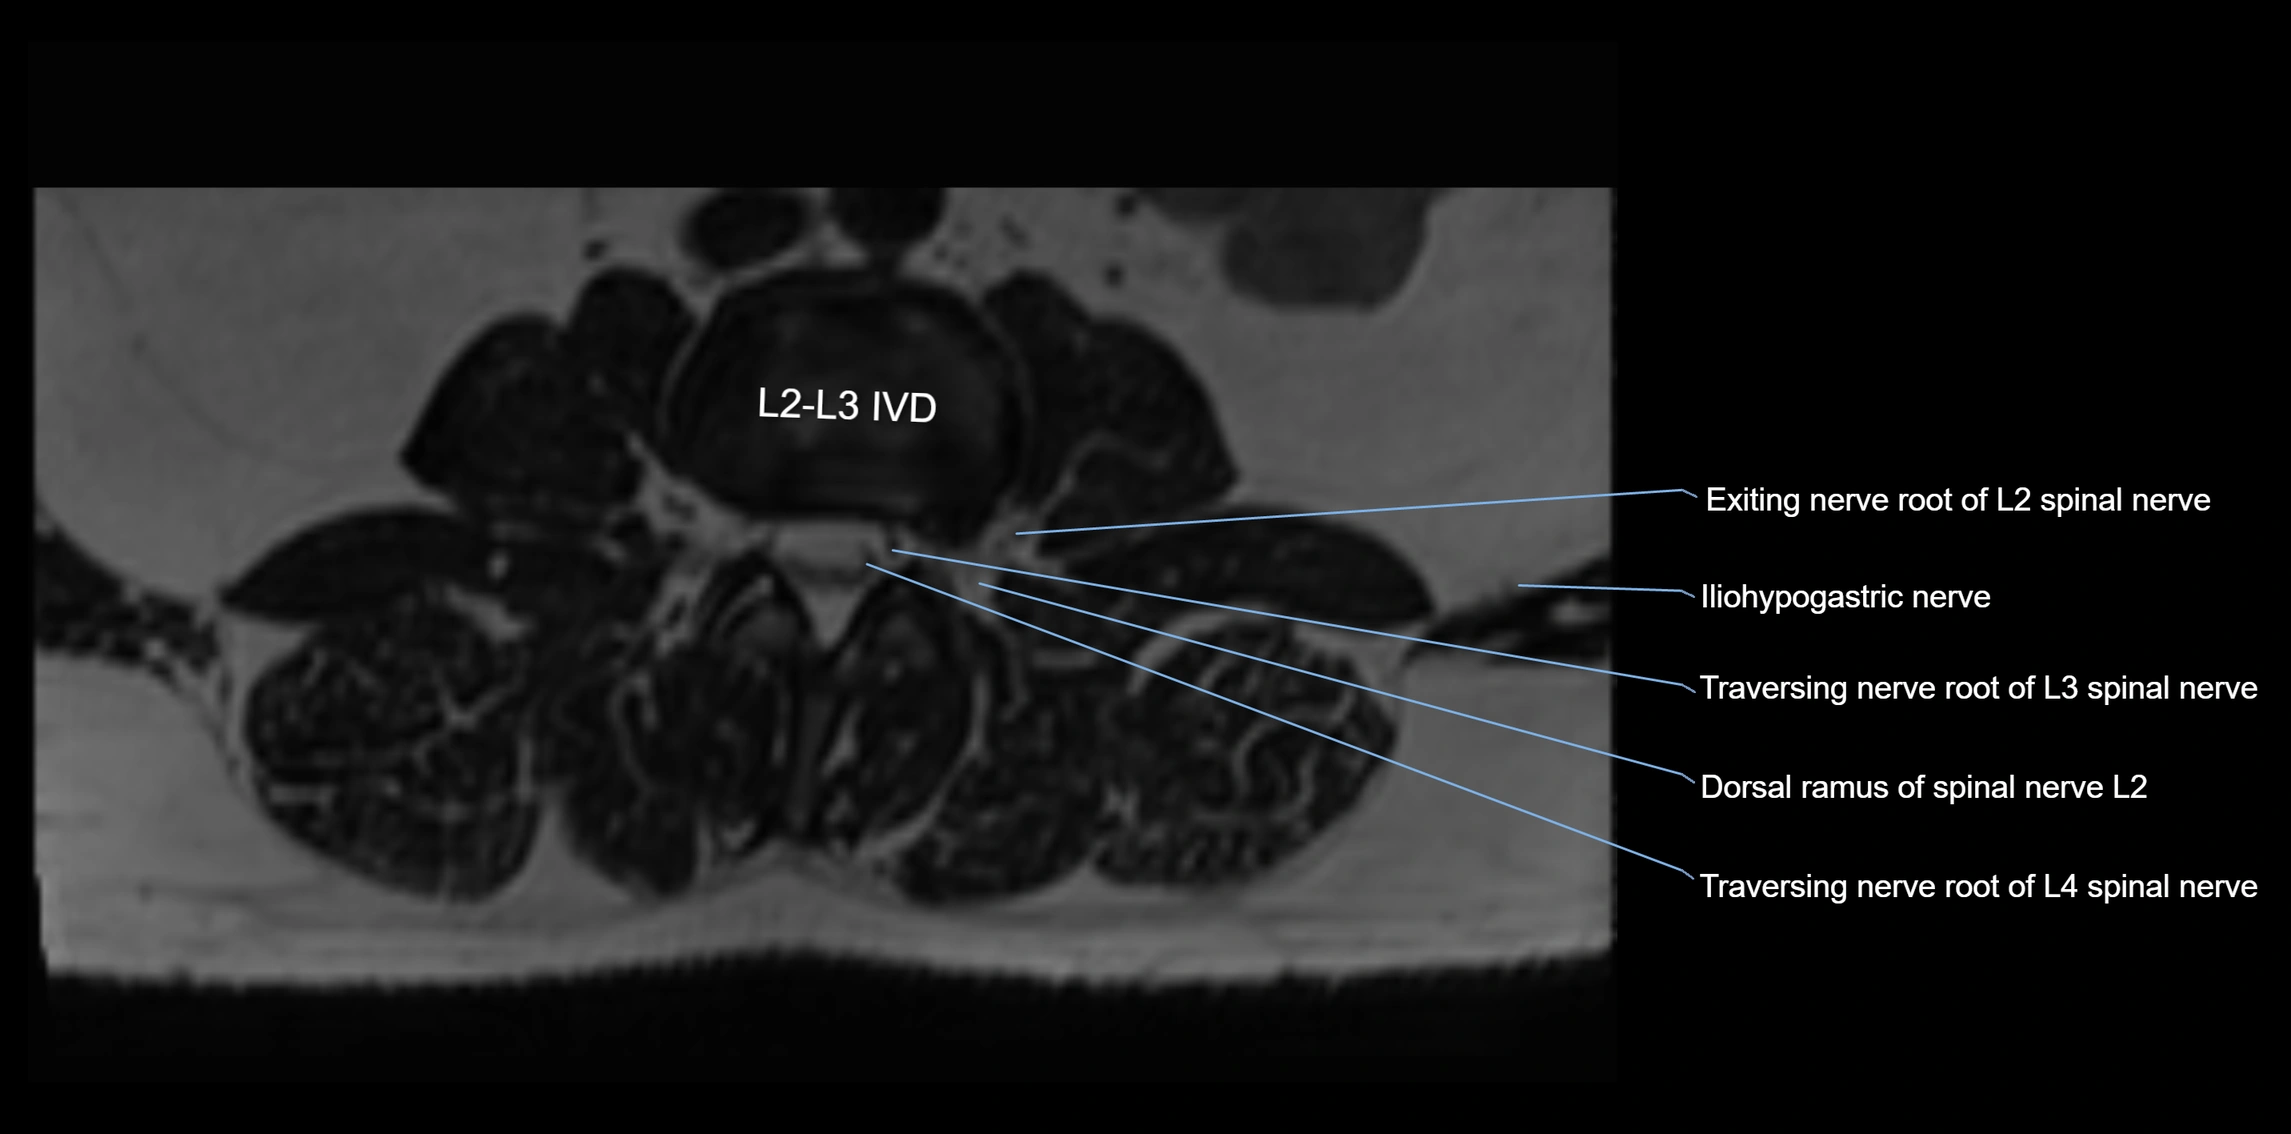

MRI image

image